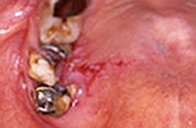

- 歯肉がん

歯肉がんは舌がんの次に多い口腔がんです。歯肉は薄いために容易に顎骨に浸潤します。レントゲン写真で骨への浸潤と破壊の程度を観察することが可能ですが、進展した歯周病とよく似た臨床所見を示す場合もあり発見が遅れることもあります。骨を含めて切除する外科処置が一般的で、二次的に放射線療法や化学療法を組み合わせます。